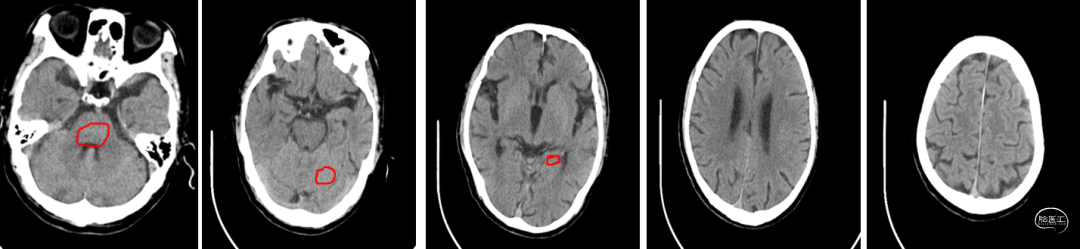

头颅CT(2024-07-25,外院):双侧基底节区,放射冠腔隙性脑梗死。

患者取平卧位置,常规消毒、铺巾和局麻右侧腹股沟下穿刺点后,穿刺置入5F动脉鞘,再以5F单弯行选择性脑动脉造影。造影示:II型主动脉弓,右侧颈内动脉C1段重度狭窄。

左侧颈动脉未见明显异常。

造影显示左侧椎动脉V1段中重度狭窄。